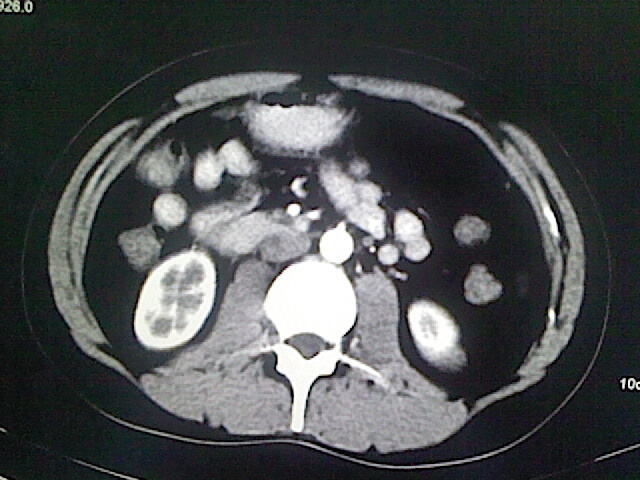

以下是引用卜一在2009-3-14 9:49:00的发言:[br]胆囊萎缩,胆囊壁不规则增厚,内部结构模糊,增强明显强化。另:肝左叶外侧段肝囊肿。支持:慢性胆囊炎!高度可疑:胆囊癌!

以下是引用余辉在2009-3-14 8:48:00的发言:[br]1)慢性胆囊炎。2)肝左叶外侧段肝囊肿。3)脂肪肝。[br]支持,胆囊萎缩,密度增高,不知b超具体有何提示,钙胆汁?结石?

以下是引用jiangjing在2009-3-14 10:18:00的发言:[br]1)慢性胆囊炎。2)肝左叶外侧段肝囊肿。3)脂肪肝。4.】建议行肝功能检查